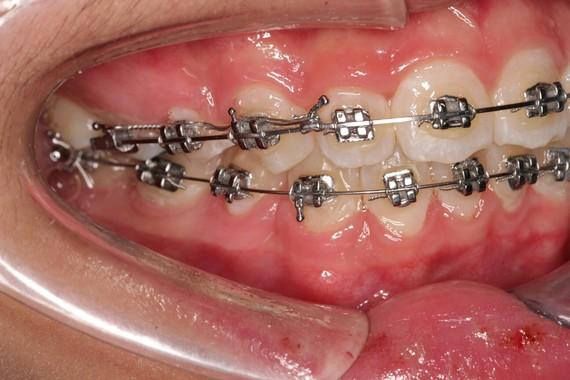

正畸治療是常見(jiàn)的治療方法之一,適用于牙齒排列不齊導(dǎo)致的輕度“凹”“凸”面型。通過(guò)佩戴牙套,如金屬牙套、陶瓷牙套或隱形牙套,對(duì)牙齒施加力量,使其移動(dòng)到正確的位置,從而改善咬合關(guān)系和面部形態(tài)。